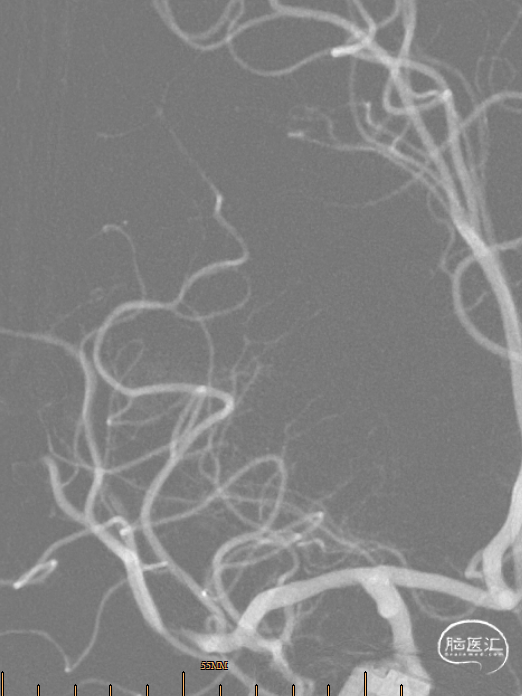

诊疗经过